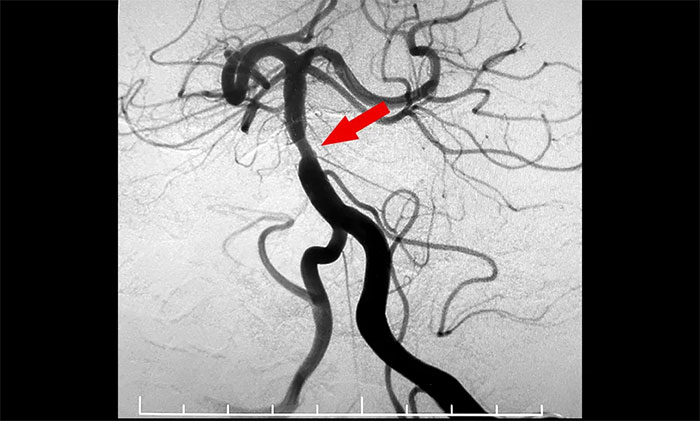

7月29日,經(jīng)過充分的準(zhǔn)備工作,席剛明教授、王貴平博士在介入團(tuán)隊(duì)協(xié)助下順利為患者實(shí)施了手術(shù)。術(shù)中兇險(xiǎn)的就是球囊擴(kuò)張狹窄,如果掌握不好擴(kuò)張球囊的位置和擴(kuò)張速度,勢必造成更復(fù)雜的血管夾層甚至出血。歷時(shí)兩個(gè)多小時(shí)奮戰(zhàn),席剛明教授、王貴平博士憑借豐富的經(jīng)驗(yàn)及精準(zhǔn)的手法順利地于基底動(dòng)脈狹窄處進(jìn)行了球囊擴(kuò)張,并順利置入支架,造影可見左側(cè)椎動(dòng)脈、基底動(dòng)脈、雙側(cè)大腦后動(dòng)脈、雙側(cè)小腦上動(dòng)脈、左側(cè)小腦前下動(dòng)脈顯影可,基底動(dòng)脈狹窄明顯改善。最終,患者基底動(dòng)脈得以順利開通,手術(shù)獲得圓滿成功,打開了患者的“生命通道”。

▲ 基底動(dòng)脈順利開通